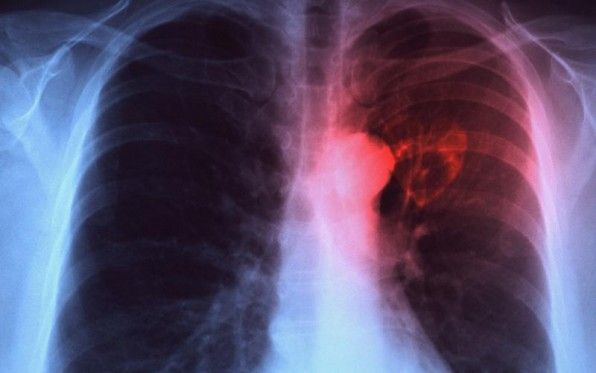

Αμερικανοί εππιστήμονες εκπαίδευσαν ένα σύστημα τεχνητής νοημοσύνης να μελετά ακτινογραφίες και να κάνει διαγνώσεις φυματίωσης. Το σύστημα αναμένεται να βοηθήσει μελλοντικά γιατρούς απομονωμένων περιοχών και αναπτυσσόμενων χωρών, που δεν έχουν πρόσβαση σε εξειδικευμένους ακτινολόγους.

Σύμφωνα με άρθρο του επιστημονικού εντύπου Radiology, ερευνητές του Πανεπιστημιακού Νοσοκομείου Τόμας Τζέφερσον της Φιλαδέλφεια, με επικεφαλής τον δρα Πάρας Λακχανί, τροφοδότησαν με ακτινογραφίες (θετικές και αρνητικές στη φυματίωση) δύο διαφορετικά μοντέλα τεχνητής νοημοσύνης (AlexNet και GoogleNet).

AlexNet και GoogleNet διαφώνησαν στο 12% περίπου των ακτινογραφιών που κλήθηκαν να διαγνώσουν. Τελικά, οι ερευνητές συνδύασαν τα δύο μοντέλα, πετυχαίνοντας ακρίβεια 96% στη διάγνωση της φυματίωσης. Όταν το σύστημα τεχνητής νοημοσύνης συνδυάσθηκε με την εμπειρία ενός ακτινολόγου, το ποσοστό ακρίβειας έφθασε το 99%.